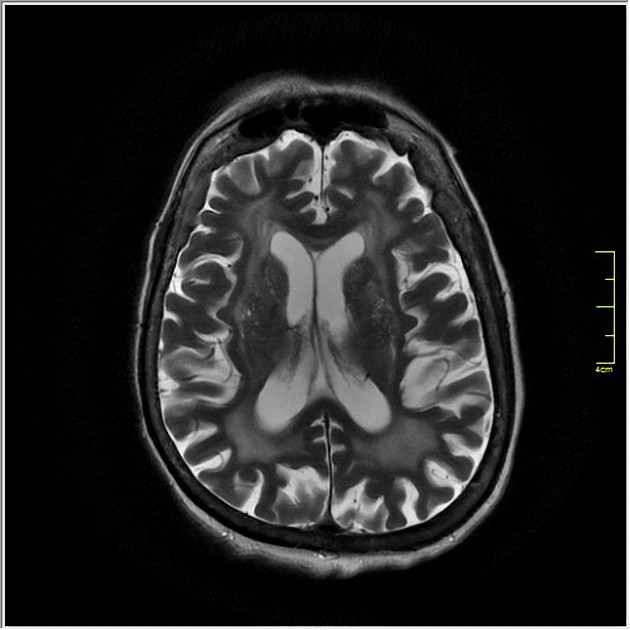

В режиме Т2 визуализируются множественные очаги гиперинтенсивного сигнала в перивентрикулярной и субкортикальной белой материи, преимущественно в лобных и теменных долях, что соответствует хронической ишемии.

Расширение периваскулярных пространств, атрофия коры и увеличение желудочков могут быть дополнительно выявлены как признаки выраженной энцефалопатии.

- Глубина ишемических изменений в белом веществе мозга определяется по интенсивности сигнала в Т2-режиме, что отражает стадию процесса.

- Степень вовлечения субкортикальных зон и базальных ядер оценивается при многоплоскостной визуализации, что важно для оценки когнитивного прогноза.

- Толщина и структура коры больших полушарий фиксируются при оценке выраженности корковой атрофии.

- Объём перивентрикулярного лейкоареоза и его распространённость сопоставимы с клиническими проявлениями.

- Наличие лакунарных инфарктов и постишемических кист визуализируется с высокой точностью, что имеет значение для стратификации риска.